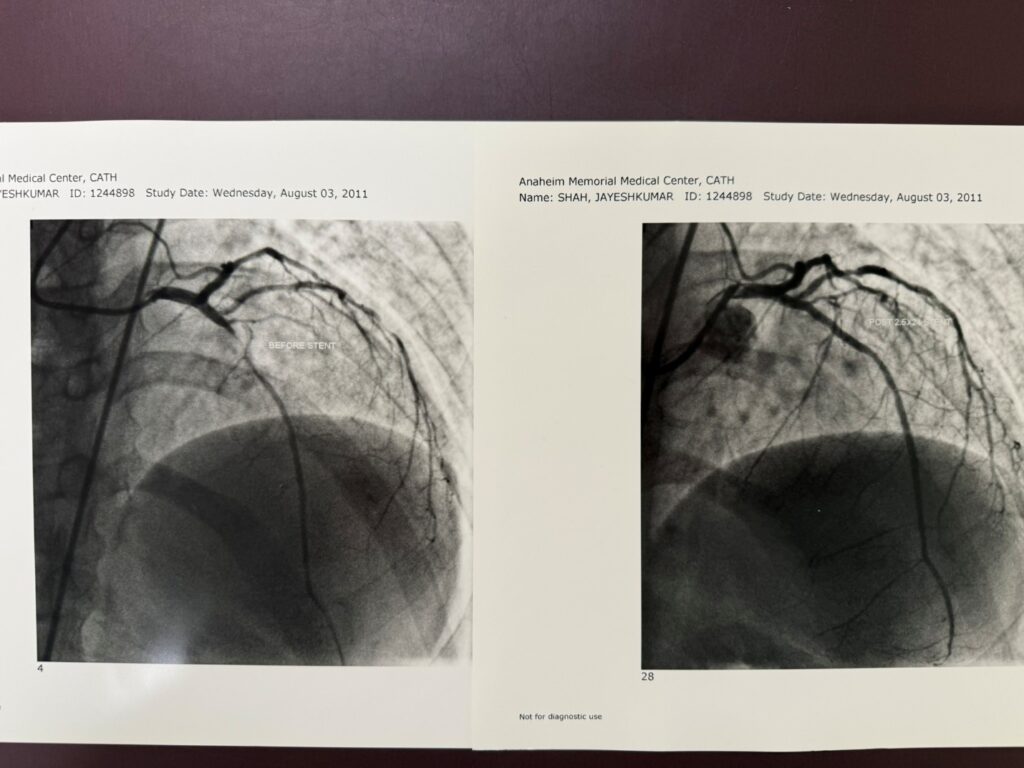

Percutaneous Coronary Intervention (PCI)

Percutaneous Coronary Intervention (PCI), commonly known as coronary angioplasty with stent placement, is a minimally invasive procedure used to open blocked or…